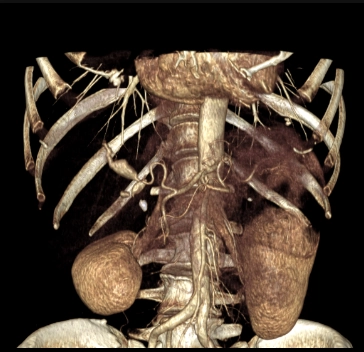

• Phình động mạch tạng (Visceral Artery Aneurysms - VAA)

• Phình động mạch thận (Renal Artery Aneurysm - RAA)